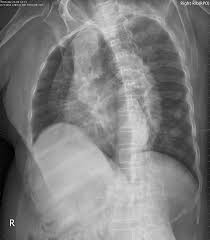

Q1: 갈비뼈 금은 X-ray에서 안 보일 수도 있나요?

A1: 네, 초기에는 X-ray에서 잘 보이지 않는 경우도 있어 증상과 촉진이 중요합니다.